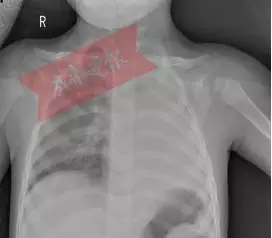

| 7月29日晚,成都1岁多的女孩豆豆(化名)经四川省某医院急诊科绿色通道快速进入重症医学科抢救。一天前还是活蹦乱跳的孩子,突然被送进重症监护室,而更令所有人大吃一惊的是,胸片显示,孩子的左肺竟然“不见了”?!

咳嗽输液突发呼吸不畅 胸片显示:左肺“不见了” 7月29日,原本身体很好的豆豆,不知为什么总会连续咳嗽,甚至嗓子都出现了沙哑,家长非常担心,赶紧带着豆豆到附近的某医院就医。可是,当输液的过程中,病情反而更加严重了,豆豆突然哮喘,气促、呼吸困难等症状。情急之下,经医院建议迅速转院到四川省某医院重症医学科进行抢救。 重症医学科副主任谢成告诉记者,接诊的时候豆豆气喘急促、口唇发绀,左侧肺部呼吸音消失,各项的生命指征都不好。重症医学科医护团队立即给豆豆气管插管、呼吸机辅助通气治疗,在维持孩子的氧合前提下,放射科顺利完成了床旁胸片检查,而胸片的结果却让在场所有人震惊:孩子的左肺竟然“不见了”?! 肺从片子上消失,医学上称为“白肺”。正常的肺部有空气进入,在 CT 片上是呈影的。“白肺”,即肺部显影呈一大片的白色状,起因一般是重症肺炎或者大量的胸腔积液。但是豆豆并没有肺部疾病史,究竟是什么原因呢?重症医学科副主任谢成告诉记者:“当时反复追问家属是否有异物呛入病史,但是孩子的父母都坚决否认。” 呼吸气道被完全堵塞 罪魁祸首竟是花生米 情急之下,重症医学科副主任谢成决定立即进行床旁纤维支气管镜探查气道情况。当纤维支气管镜进入气道时,显示屏上看到豆豆的左侧主支气管被完全堵塞。如果不尽快解除堵塞,后果不堪设想。随后,经过同儿外科、儿科、耳鼻喉科、麻醉科等多学科专家成立专家小组会诊病情,结合小女孩的年龄特点,最终锁定支气管内异物或是塑型性支气管炎。